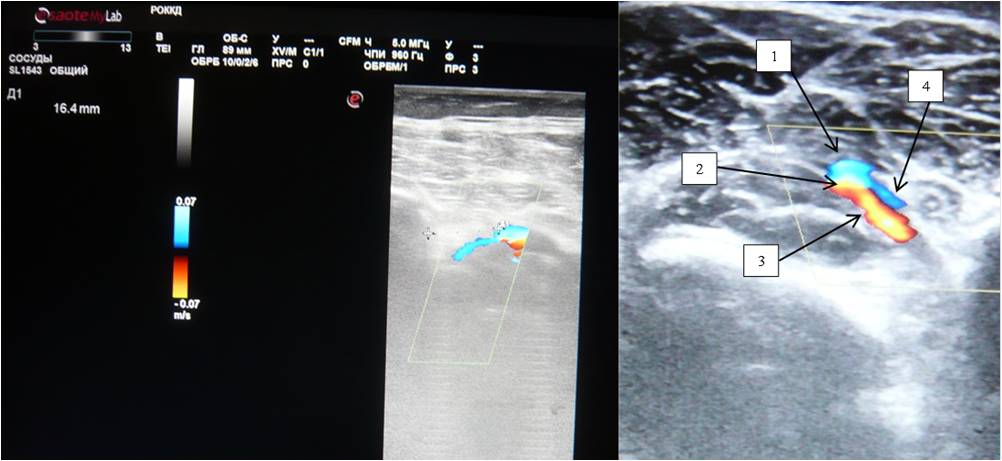

Interesting data on the location of PA were obtained by DS. In the proximal part of the popliteal fossa, PA was located relative to the midline, and in the distal part it was displaced laterally and coursed 1.51 ± 1.4 cm medial to the head of fibula (Figure 4).

Fig. 4. Duplex scan of the bifurcation region of the popliteal vessels — the distance from the head of fibula is 16.4 mm.

Notes: (1) Popliteal vein; (2) Popliteal artery; (3) Anterior tibial artery; (4) Anterior tibial veins.